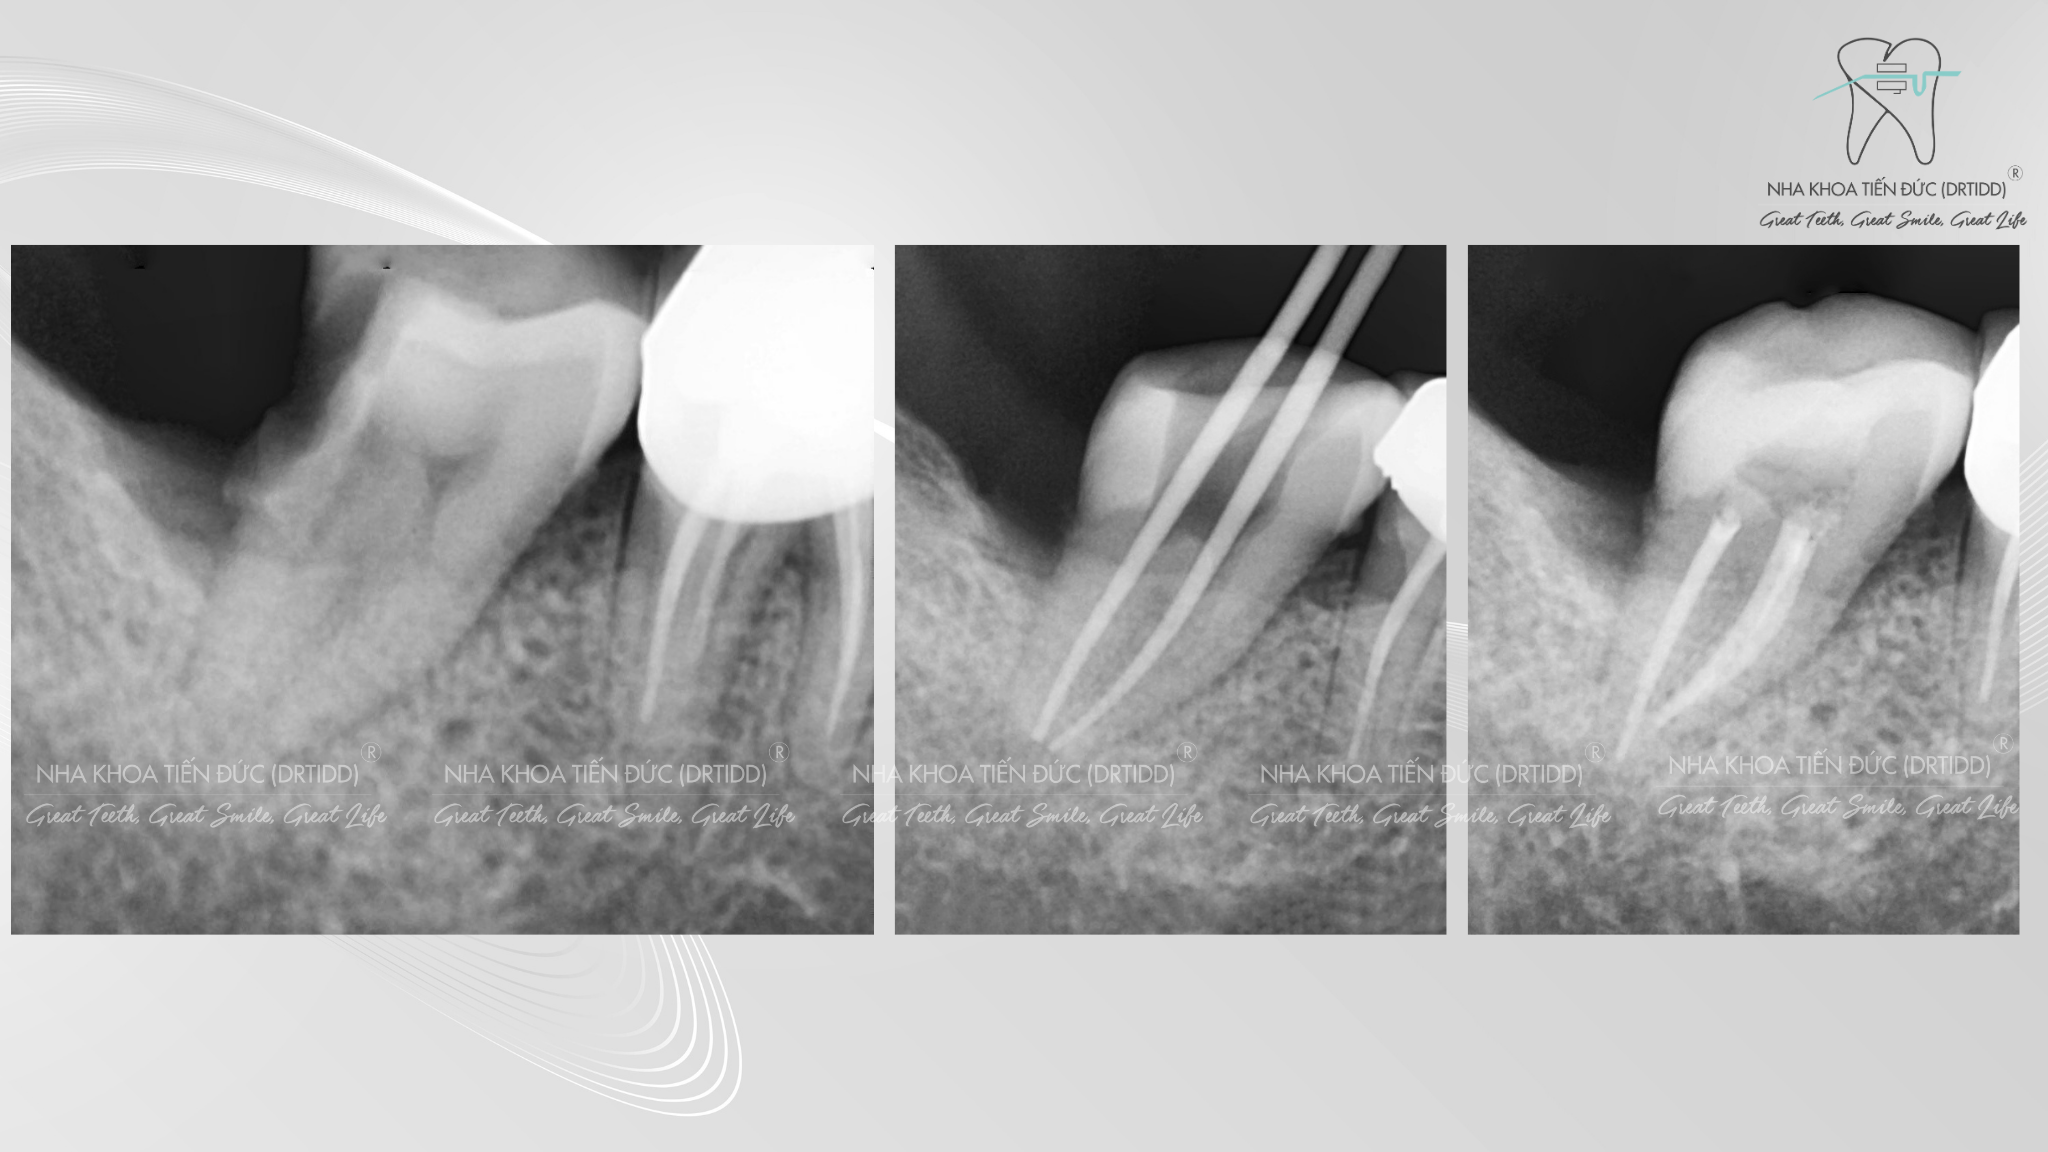

Hình ảnh Xquang điều trị tủy răng tại Nha Khoa Tiến Đức

- Điều trị tủy hay còn gọi là nội nha, là quá trình loại bỏ hết phần tủy răng (cả tủy buồng và tủy chân). Sau khi lấy hết mô tủy, bác sĩ sẽ tiến hành làm sạch, tạo dạng ống tủy và hàn kín lại hệ thống ông tủy.

- Bác sĩ điều trị nội nha sẽ khám răng cho bạn, đánh giá tình trạng tổn thương , thu thập dữ liệu bao gồm hình ảnh và X- quang .

- Bác sĩ bắt đầu thực hiện quá trình lấy bỏ tủy viêm bằng máy nội nha kết hợp với trâm nội nha cá nhân đảm bảo vô khuẩn tuyệt đối .

- Sau khi làm sạch ống tủy bác sĩ sẽ trám bít kín lại ống tủy theo 3 chiều không gian bằng vật liệu tương thích sinh học cao với cơ thể.